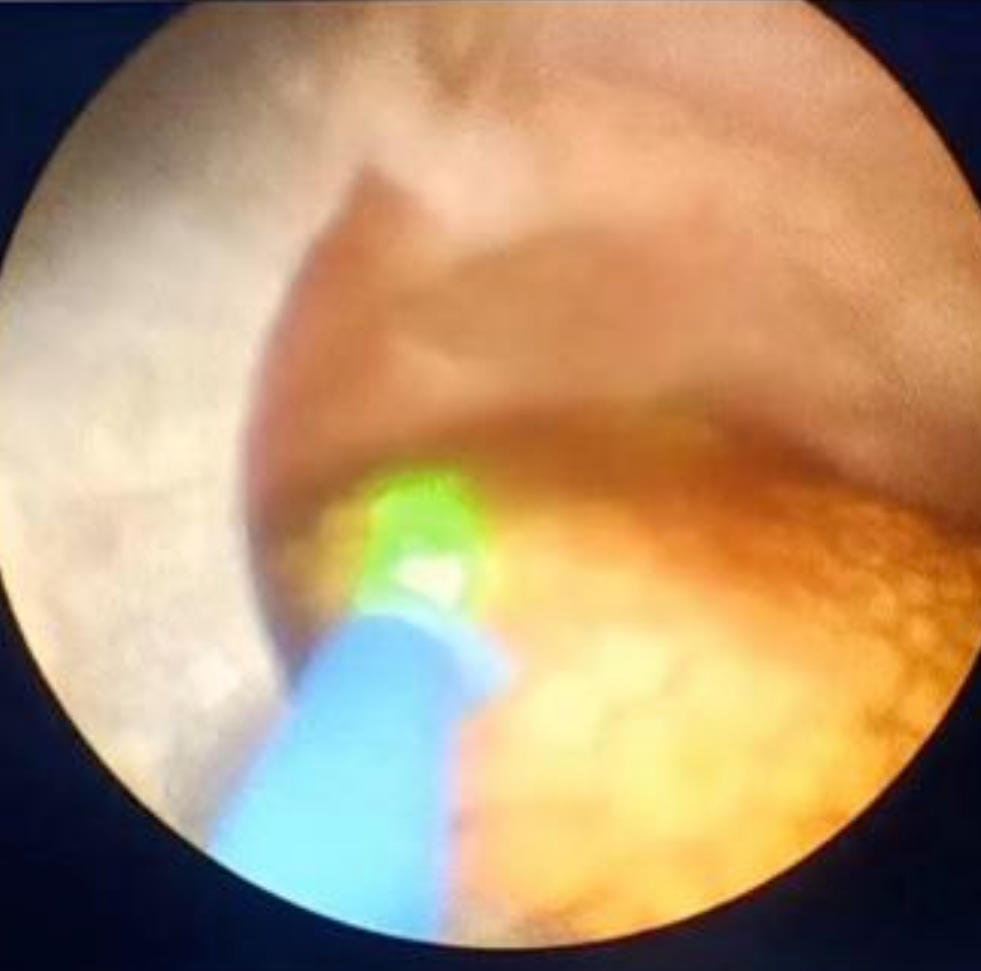

③输尿管镜碎石术(URS):经尿道插入纤细的内窥镜,直达输尿管和肾脏,用激光将结石击碎并取出。